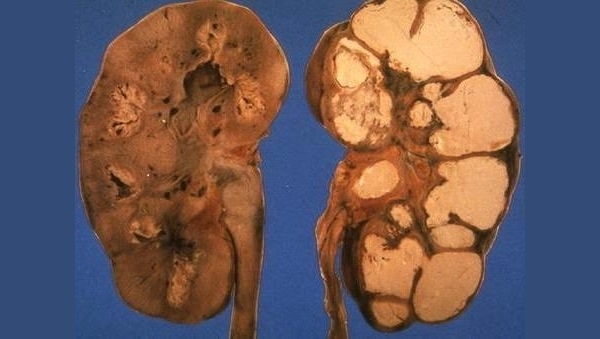

При прогрессировании инфекционного заболевания в тканях почки наблюдается образование каверн и полостей. Орган практически «расплавляется» изнутри.

- Тотальная деструкция. На данном этапе заболевание вызывает обширное поражение почечной ткани, иногда почка становится одной большой полостью, стенками которой являются остатки тканей органа.

Почечный туберкулез опасен тем, что он вызывает необратимые изменения в почечных тканях. При образовании каверн и полостей разрушаются структуры почки, что приводит к полной утрате функции органа.

Еще одним методом лечения является кавернэктомия (удаление полости). В более тяжелых случаях может быть проведена резекция всего органа или его части. Полностью почка удаляется лишь в запущенных случаях, при тотальном поражении тканей.